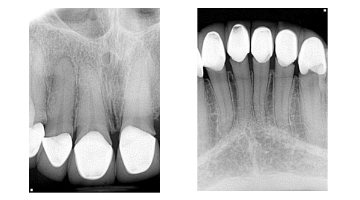

It’s one thing to see an overhang or open margin on one crown or filling, but when you see an entire mouthful of yuck, what do you tell the patient? I’m not a fan of throwing my colleagues in dentistry under the bus, but when I see questionable dental work, I believe the patient needs to know that there are concerns that affect two things: 1. the integrity of the tooth/teeth, and 2. the financial impact it could have.

So, when this patient presented to my office saying that all of her crown work was very recently done, I did a double take and asked, “Really?” Oy vey. Not fun. I recently posted this case in DE’s Breakthrough Clinical Facebook group. The responses are all enlightening and worth your read. With that being said, what would you say to this patient?